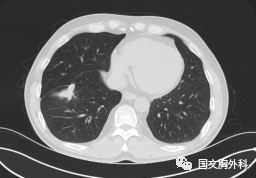

這個(gè)病人檢查胸部CT如圖3:根據(jù)影像學(xué)考慮是惡性腫瘤,行手術(shù)治療后病理回報(bào):“肺膿腫,合并炎癥纖維組織增生”,因此“肺占位”不代表就是惡性腫瘤,診斷金標(biāo)準(zhǔn)是病理診斷。如果檢查后發(fā)現(xiàn)“肺占位”先不要驚慌,及時(shí)就診請(qǐng)??漆t(yī)生會(huì)診指導(dǎo)治療才是關(guān)鍵。